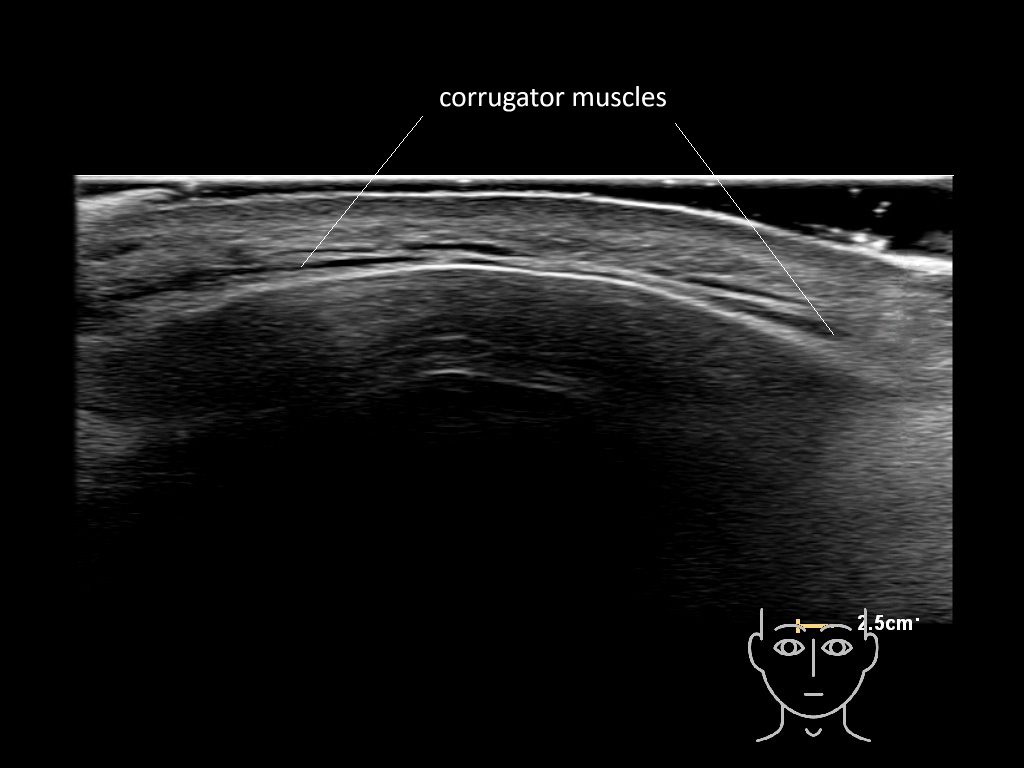

In this section you will learn more about the different layers of the face with the use of ultrasound. When you click on the secondary ultrasound image, you will see the different structures as an overlay. This will help to train yourself to recognize the different layers of the face.

Study the first image to recognize the different layers. If you are sure about the layers, swipe to the second image to view the answer (if applicable).